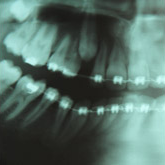

So what is orthodontics? Orthodontics is a specialised area of dentistry that straightens or moves teeth to improve their appearance and how they work. It can also help the way that the upper and lower teeth bite together so that the biting pressure is spread more evenly over the teeth. Problems in biting pressure can sometimes cause chipped, worn, or loose teeth and can place the chewing muscles and joints under stress.

Using fixed, removable or invisible braces, depending on the treatment required, constant and gentle pressure is put on the teeth or the jaws to move them into a more favourable position. This will help you to eat more comfortably, clean your teeth more easily and as a result help to prevent tooth decay and gum disease.